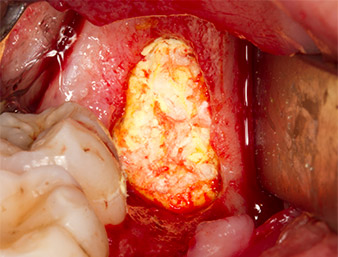

virutas óseas

Imagen 13: Las virutas óseas procedentes del campo quirúrgico se guardaron en un una solución salina estéril.

A continuación, el tejido óseo autógeno (figura 13) se incorporó en el alvéolo y en el defecto óseo circundante (figura 14). Un velo de colágeno sirvió de protección para el nervio expuesto y cubrió las virutas óseas hasta el nivel del hueso (figura 15). Se aplicaron puntos de sutura con hilos Vicryl de grosor 4.0, que cerraron los tejidos blandos abiertos (figura 16). Tras la operación, se prescribió un preparado de ibuprofeno (Seractil 400 mg 3x1) y un antibiótico con amoxicilina y ácido clavulánico (Augmentine 1g 2x1).

La parte apical del alvéolo

Imagen 14: La parte apical del alvéolo se cubrió con el tejido autógeno.